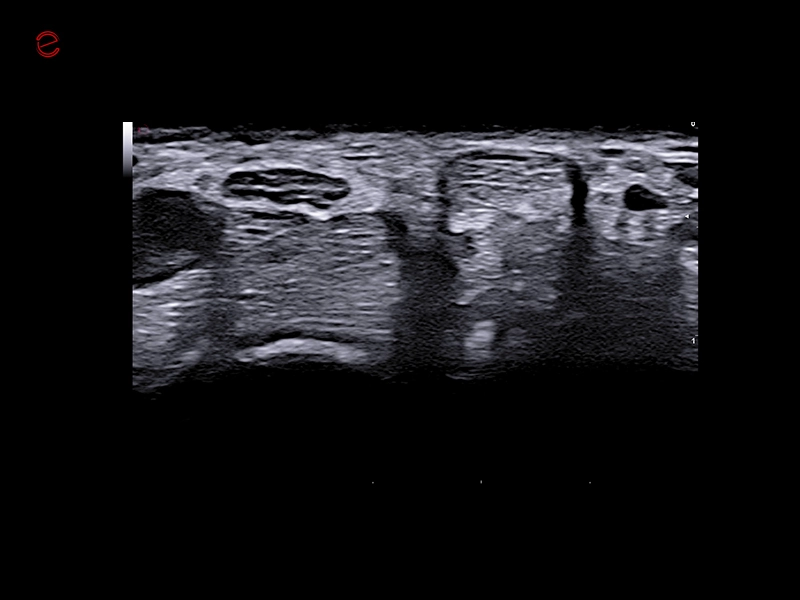

MyLab™C25 - IHX muscle

MyLab™C25 - IHX muscle